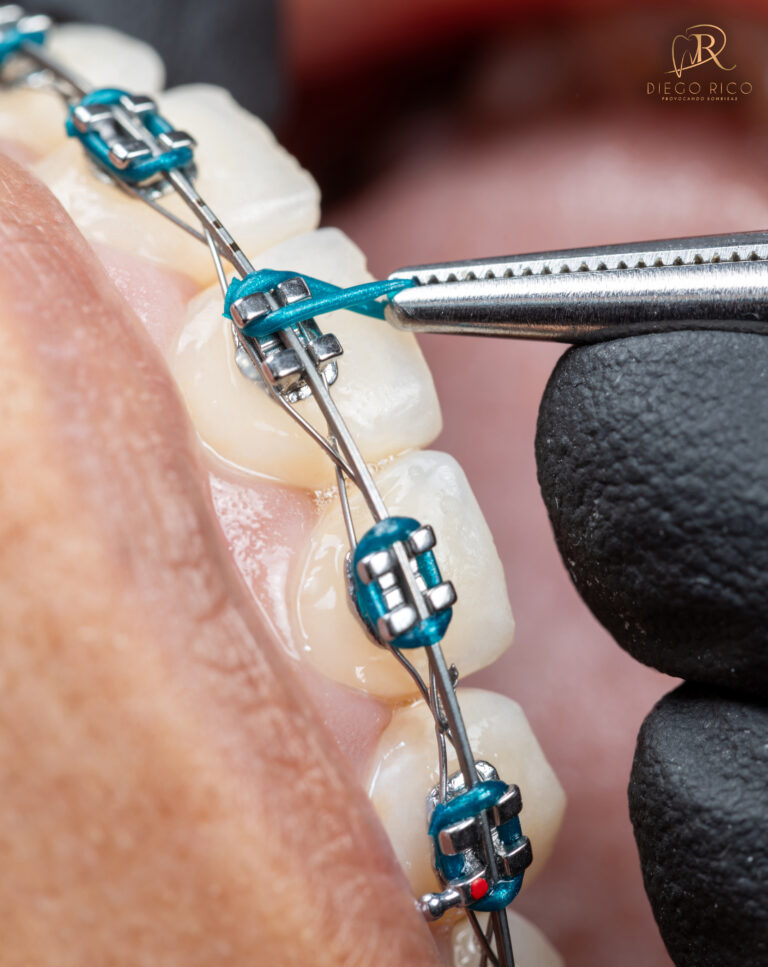

Ortodoncia

La ortodoncia corrige los defectos de la posición dental para mantener una sonrisa, perfecta y sana. Con la Dra. Lizeth Holguín podrás corregir la posición dental de esos defectos para mantener una boca sana y perfecta. Conoce las diferentes opciones que te brindaran nuestros especialistas y los diferentes tipos de tratamientos.